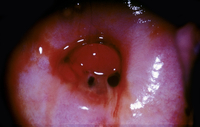

Cervical erosion

Science Photo Library; used with permission

Assessment of vaginal bleeding